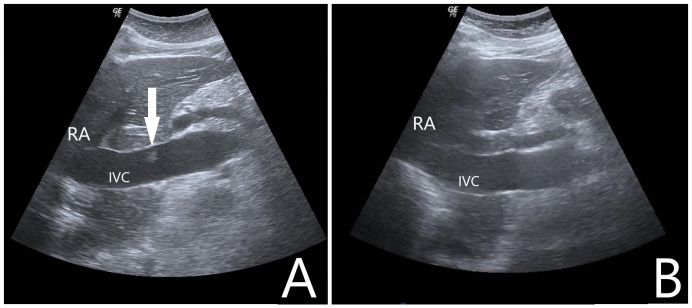

病例2:女性,69岁,农民,既往有“高血压病”“脑梗塞”“痛风”史,长期服用氨氯地平片及氯吡格雷片。主诉“胸闷胸痛2 h”于2021-10-27入院。入急诊查心电图提示存在“高侧壁、前臂、前侧壁ST段弓背向上抬高”,在送往介入室的途中出现意识不清,大动脉搏动消失,予以胸外按压、气管插管等高级生命支持。复苏期间心电监护提示室速、室颤,予以多次电除颤无法维持ROSC,征得家属同意后行ECMO支持,ECMO参数设定:转速3 400 r/min,流速3.5 L/min,吸入氧浓度100%,气流量4 L/min,成功转机后停止胸外按压,患者出现ROSC,复查床旁心电图提示“高侧壁、前臂、前侧壁ST段较前抬高”。患者出现ROSC后转运至介入室行经皮冠脉造影提示左前降支近中段次全闭,予行冠状动脉造影术+ 冠状动脉成形术+ 药物洗脱冠状动脉支架植入术+ 主动脉球囊反博泵置入,术前ECMO上机后使用肝素4 500 U,入导管室测ACT 185 s,术中追加肝素1 000 U。返回急诊ICU后给予全身肝素化抗凝,每2 h监测一次APTT,目标APTT维持在60~80 s。入院当天查心脏彩超提示LVEF:20%,左室壁运动明显减弱;入院后第1天患者口鼻腔、穿刺处大量渗血及皮下血肿,血红蛋白进行性下降,给予输红细胞悬液6 U、新鲜冰冻血浆1 000 mL并调整肝素抗凝强度使得APTT维持在50~60 s。入院后第4天复查心脏彩超提示LVEF:55%,心肌活动较前好转,并已脱离血管活性药物,遂撤除ECMO,撤机前ECMO参数设定:转速2 300 r/min,流速2.0 L/min,吸入氧浓度50%,气流量3 L/min。在拔除ECMO导管后即刻行超声筛查发现下腔静脉至右心房入口有血栓形成,长约7.2 cm,宽0.4 cm,随血流飘动(如图 2A、2B所示),筛查下肢其他部位未见明显血栓形成,遂给予依诺肝素钠100 IU/kg皮下注射每12 h一次治疗。入院后第5天行超声检查下腔静脉未见明显异常回声(如图 2C所示)。住院期间患者未出现过下腔静脉综合征或肺栓塞的症状或体征。入院后第8天患者转心内科病房,康复后出院随访1个月未遗留任何中枢神经系统并发症。

| A:下腔静脉纵向超声扫描显示下腔静脉至右心房入口有血栓形成;B:下腔静脉水平超声扫描显示下腔静脉内漂浮的血栓影;C:经治疗后超声在下腔静脉未见明显异常回声;RA:右心房,IVC:下腔静脉 图 2 撤离ECMO后即刻行下腔静脉超声检查 |